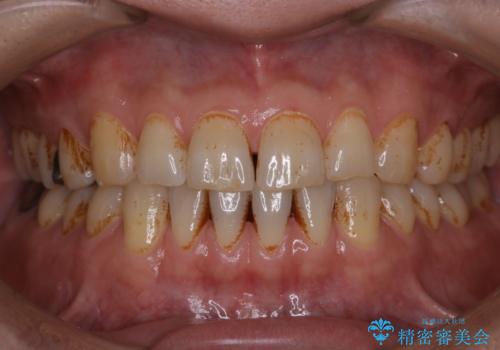

タバコとコーヒーによる頑固な着色落とし

- 毎日の喫煙とコーヒーを飲むことにより、ひどく着色がついてしまったとのことです。PMTC60分コースを行いました。